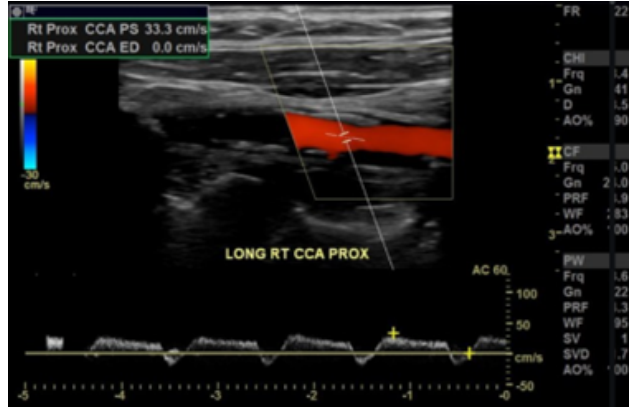

Observe a imagem a abaixo, extraída de um estudo da carótida comum direita.

Assinale a alternativa

CORRETA

.

O padrão de fluxo representado é característico de normalidade.

O padrão de fluxo é característico da fístula arteriovenosa.

O padrão de fluxo representado é conhecido como "tardus-parvus".

O padrão de fluxo representado é conhecido como "staccatto".

O padrão de fluxo representado indica kinking (acotovelamento) da carótida.